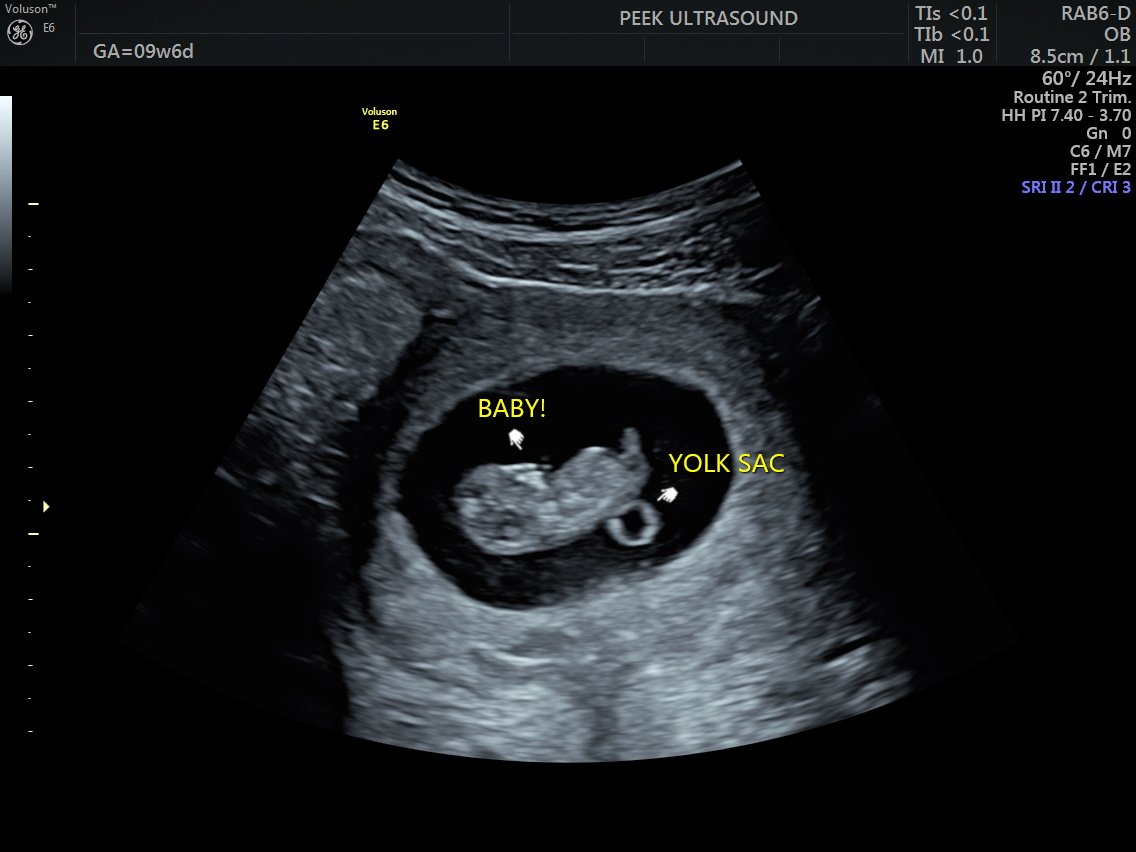

• 1st Trimester (8+ weeks) — a magical look at your little one’s developing shape, showing the full body rather than close-up facial details. You may see baby’s head, arms, and legs, and even catch movements like tiny wiggles and jumps on the screen (see our Love at First Sight scan)

Here are some general milestones:

• Baby & Heartbeat (6+ Weeks):

Around 6 weeks, baby begins to appear on an transabdominal scan, although they’re still quite small. By 7 weeks, a heartbeat is clearly visible with proper positioning and imaging technique

Every body is different, every menstrual cycle is variable, and every pregnancy is unique. Rest assured, Kayla brings expert care and personalized attention to every session, ensuring you receive the best possible experience at every stage.